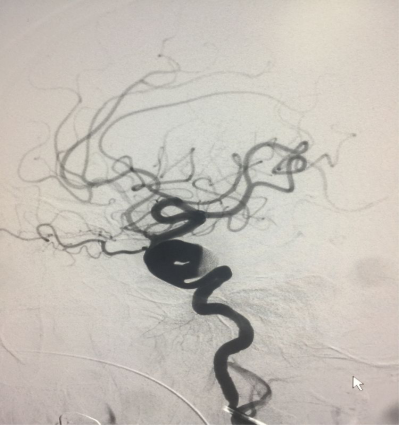

因为要给患者省钱,准备密网支架十动脉瘤内弹簧圈疏松填塞,先在动脉瘤流出道放一圈作为支柱支撑

然后释放支架并开始在动脉瘤流入道填塞弹簧圈

已可见流出道造影剂滞留,希望以后有血栓形成